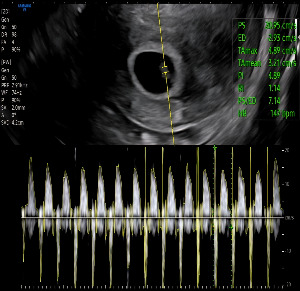

찹쌀이의 두 번째 초음파 진료를 받는 날이었다.

5주 차 초음파에서 아기집과 난황, 작게 모습을 드러낸 찹쌀 이를 만났지만

그날은 피고임이 많아 심장소리는 확인하지 못했다.

KakaoTalk_20250824_200615364_02.jpg 찹쌀이의 7주차 초음파

의사 선생님이 화면을 가리키며 말했다.

“0.96cm네요. 아주 좋습니다.

그리고… 심장도 잘 뛰고 있어요.

평균 심박수 147 bpm입니다.”